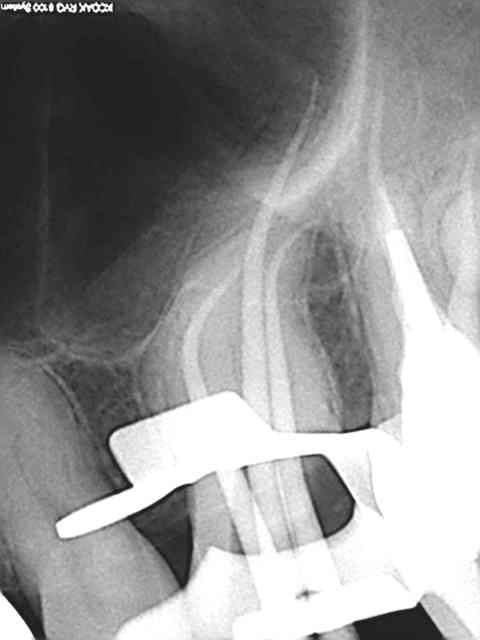

> 40 mn canal palatin xxl !

Merci. 3 récapitulations s1-r25 pour arriver au bout. je n'ai jamais vu un instrument aussi efficace que le r25, on croirait une ampliation au 50, en insistant un peu il n'y a plus de racine ! )))

Ton matériau d'obturation est confiné dans l'endodonte, je ne vois pas de dépassement de gutta, tes cones sont bien ajustés, je ne vois pas de déchirement apical.